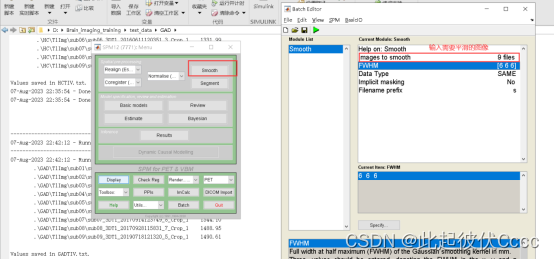

2.5 对图像进行平滑

运行spm12,点击Smooth,按下图操作,平滑核大小参考文献选择。